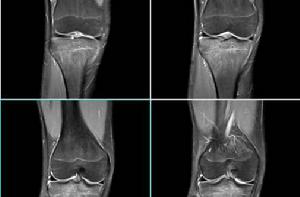

滑膜炎病史原因及調養:

造成滑膜炎,導致關節水腫的疾病很多,如類風濕性關節炎、骨性關節炎、滑膜結核、化膿性關節炎、創傷性關節炎等等,不同疾病導致的滑膜滲出增多、關節積液,其治療方法自然不同,無法一概而論。現在介紹一下最常見的單純性滑膜炎的治療:1、充分臥床休息,避免關節負重,促進關節積液吸收。2、口服非甾體類抗炎藥3、關節局部理療。4、必要關節穿刺抽液,並行關節封閉。而滑膜結核、絨毛色素結節性滑膜炎等滑模病變,都有其相應的治療方法,這裡就不一一介紹了。而至於你患的是哪種病變,還需進一步檢查明確。 水腫病人應儘量少食鹽,每日食鹽最好約1.5克(不到半錢),通常病人較易接受。這樣小量的食鹽縱使全部瀦留在體內,每6日亦只增加1公斤體重罷了。完全不給鹽,則飲食無味,影響病人的食慾。健脾補腎、利小便的食物,如苡米、赤小豆、扁豆、芡實、蓮子、蘿蔔、鱔魚、鴨肉、豬肉等,均宜多吃。